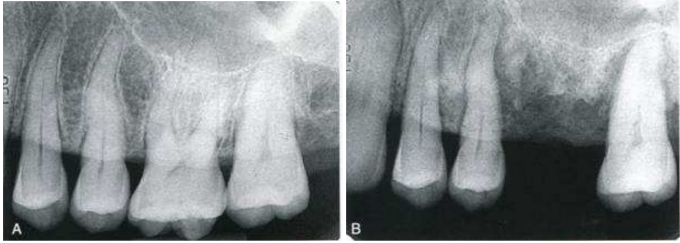

71.一位中年男性因鼻咽癌接受頭頸部放射線治療,左圖為治療前X光片,右圖為放射線治療半年後的X光片影像呈現牙齒及齒槽 嵴周邊有骨硬化和大量骨破壞情形,在鑑別診斷後,下列何種病變最有可能?

(A)Recurrence of the malignant neoplasm (B)Actue osteomyelitis (C)Radiation therapy-induced osteoradionecrosis (D)Bisphosphonate-induced osteonecrosis